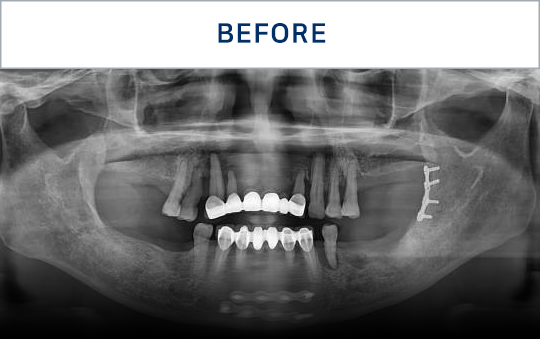

전후가 명확한 결과, 그 결과가

곧 신길플란트치과의 신뢰입니다.